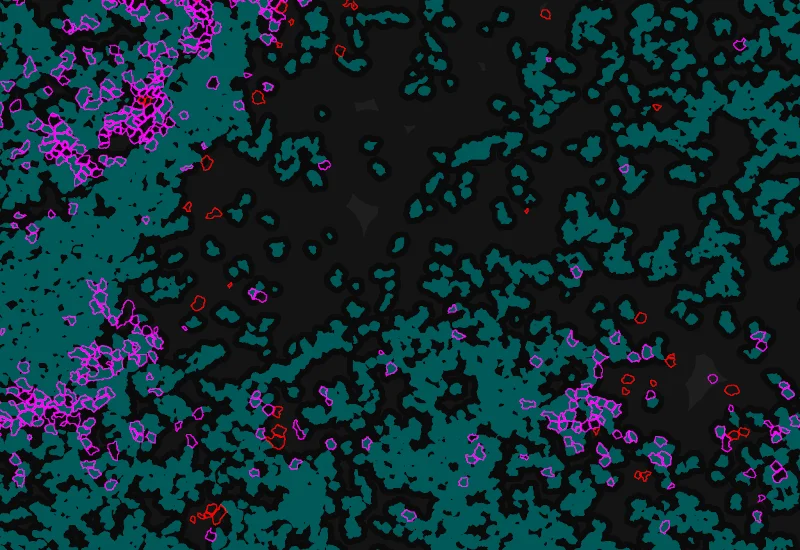

Phenotype 1 and Phenotype 2 detection

Phenotype 1 to 2 proximity 0-5μm

Phenotype 1 to 2 proximity 5-25μm

Phenotype 1 to 2 direct contact